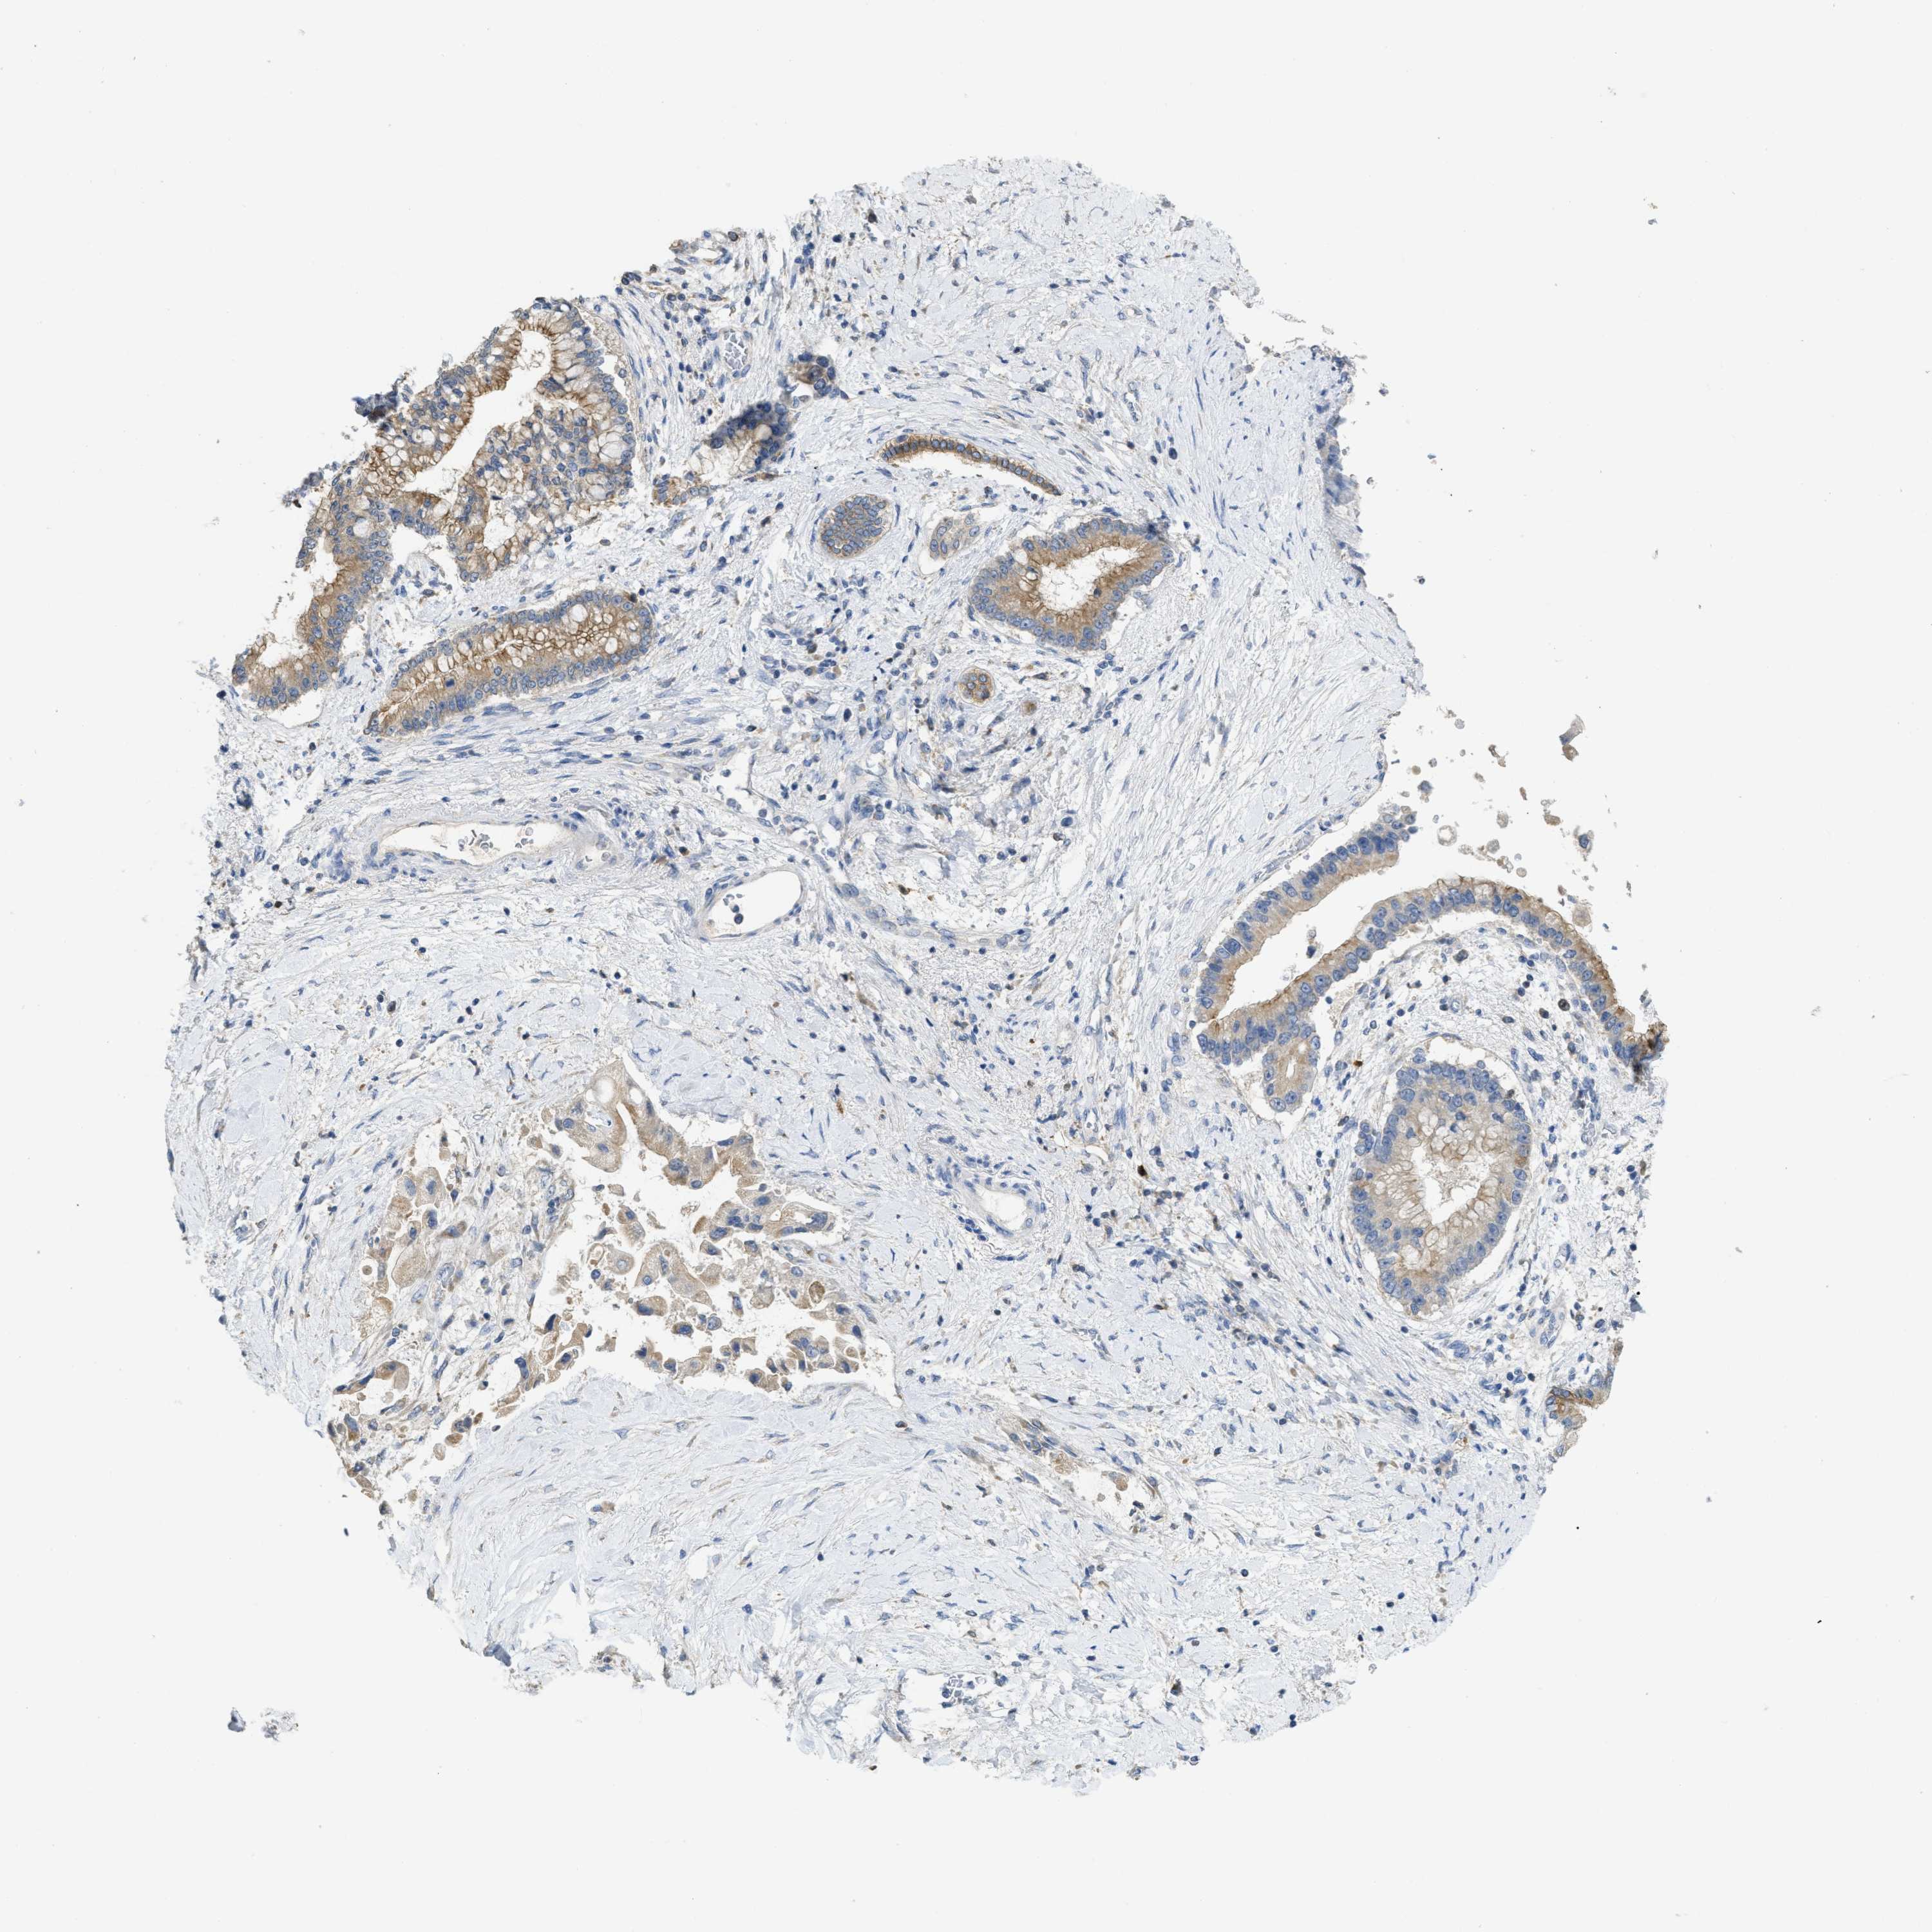

LIVER CANCER - Protein expressioni

A mouse-over function shows sample information and annotation data. Click on an image to view it in a full screen mode. Samples can be filtered based on level of antibody staining by selecting one or several of the following categories: high, medium, low and not detected. The assay and annotation is described here.

Note that samples used for immunohistochemistry by the Human Protein Atlas do not correspond to samples in the TCGA dataset.

Antibody stainingi

Antibody staining in the annotated cell types in the current human tissue is reported as not detected, low, medium, or high, based on conventional immunohistochemistry profiling in selected tissues. This score is based on the combination of the staining intensity and fraction of stained cells.

Each image is clickable and will lead to virtual microscopy that enables deeper exploration of all samples and also displays staining intensity scores, fraction scores and subcellular localization as well as patient and tissue information for each sample.

Antibody HPA018150

Antibody HPA026834

Staining

High

Medium

Low

Not detected

Intensity

Strong

Moderate

Weak

Negative

Quantity

>75%

75%-25%

<25%

None

Location

Nuclear

Cytoplasmic/membranous

Cytoplasmic/membranous,nuclear

Cholangiocarcinoma

Carcinoma, Hepatocellular, NOS